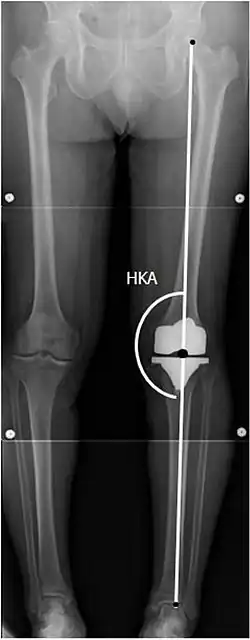

CRT: Ángulo cadera-rodilla-tobillo, que idealmente está entre 3° en varum y 3° en valgum desde un ángulo recto.[54] -

- CFF: ángulo del componente femoral frontal. Por lo general, se considera óptimo cuando se encuentra entre 2 y 7° en valgo.[55]

- CTF: ángulo del componente tibial frontal, que se considera óptimo cuando se encuentra en ángulo recto. En general, se ha encontrado que una posición en varo de más de 3 ° aumenta la tasa de falla de la prótesis.[55] -

- CTL: ángulo del componente tibial lateral (o sagital), que está idealmente posicionado de modo que la tibia esté flexionada de 0 a 7° en comparación con un ángulo recto con la placa tibial.[55]